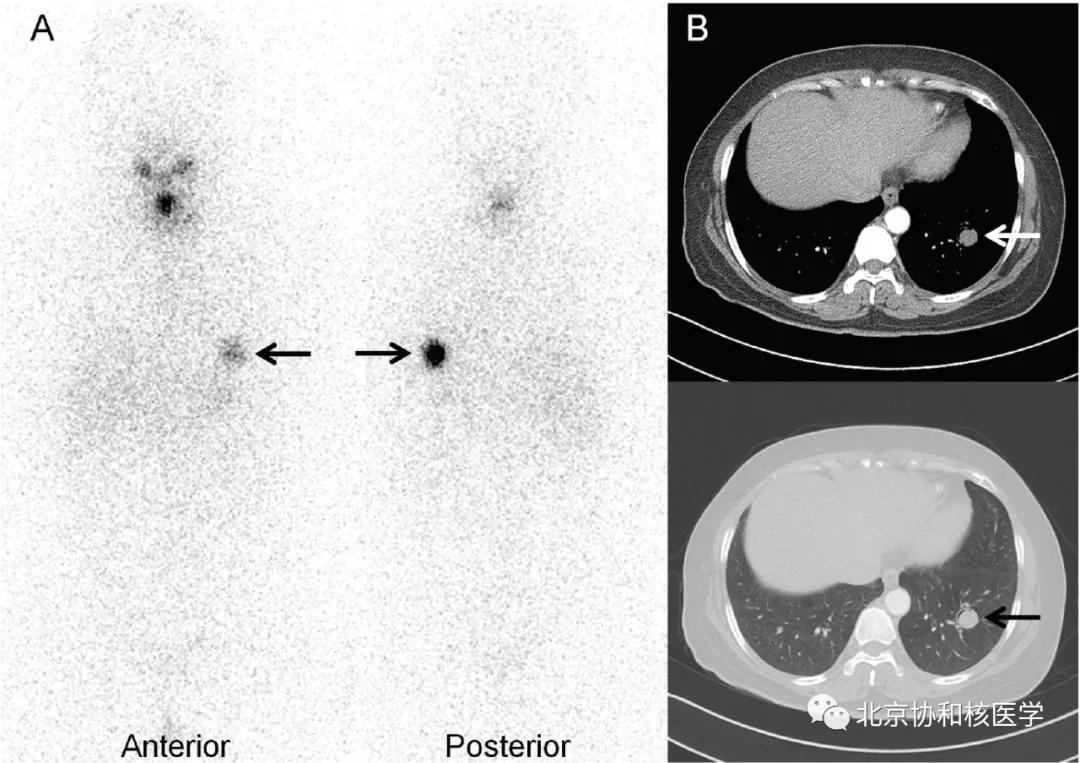

肺鳞癌所致碘摄取(后位图像),同时可见颈部甲状腺残余病灶: